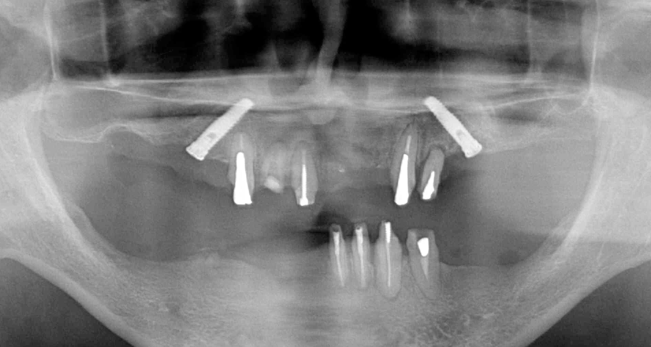

術後レントゲンです。このように斜めにインプラントをいれることにより、上顎洞への骨移植をさけることができます。これはオールオンフォーのインプラントを行っている歯科医ならではの発想です。

もし、前歯が悪くなった場合、さらに2本インプラントを追加すれば固定式の歯をいれることができます。